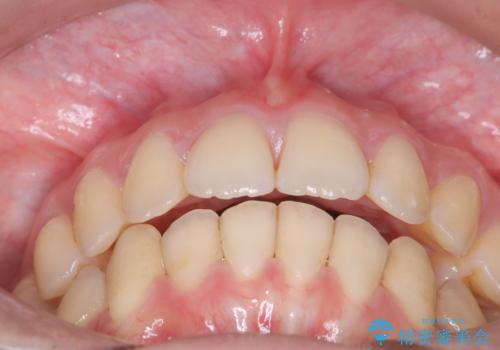

- 前歯の突出を主訴に来院されました。

アンカースクリューとインビザラインを用いて遠心移動を行うことでできる限り前歯を下げて叢生の改善を行いました。